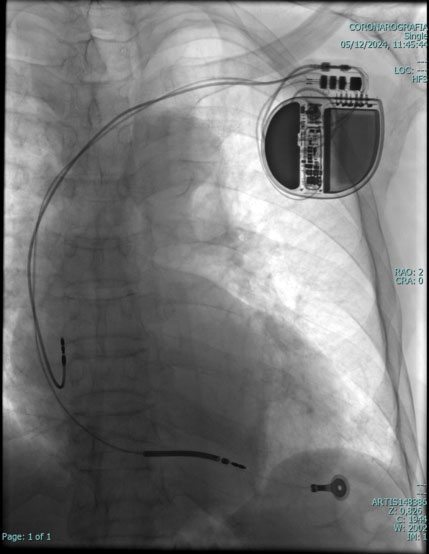

Il Pace Maker è un piccolo apparecchio elettronico che viene inserito nel corpo del paziente mediante una breve incisione, solitamente sotto la clavicola sinistra. Il Pace Maker è collegato al cuore mediante uno o due fili elettrici (detti “cateteri”), introdotti in una vena della spalla.Il pacemaker interviene in aiuto del cuore quando questo batte troppo lentamente; tuttavia non impedisce al cuore di funzionare autonomamente nei momenti in cui batte in modo regolare.

Il Pace Maker è costituito da una piccola scatola di metallo liscio e leggero; le dimensioni e il peso variano a seconda del tipo e delle caratteristiche; mediamente ha una forma rotondeggiante, misura tra 5 e 6 cm da un lato, tra 4 e 5 cm dall'altro e ha uno spessore tra i 7 e i 9 mm; il peso oscilla tra 20 e 30 grammi. La scatola contiene un minuscolo computer e una batteria, che può durare, a seconda dell'uso che se ne fa, fino a 12 anni; attraverso uno o due elettrodi, a seconda delle necessità, invia al cuore piccolissimi impulsi elettrici in grado di aumentare, quando è necessario, i battiti cardiaci.

Gli impulsi elettrici trasmessi dal Pace Maker al cuore sono di bassissima intensità e non vengono assolutamente avvertiti dal paziente. Il Pace Maker viene inserito mediante una semplice procedura: in anestesia locale si pratica una piccola incisione della pelle, di pochi centimetri, nella regione alta del torace, sotto la clavicola sinistra. Si cerca quindi una vena per l'introduzione dei cateteri, che vengono guidati fino al cuore, controllandone il percorso mediante la radioscopia; dopo aver controllato che i parametri elettrici siano regolari, i cateteri vengono collegati al Pace Maker che viene infine inserito in una piccola tasca sotto la pelle; tutto ciò avviene in modo del tutto indolore.